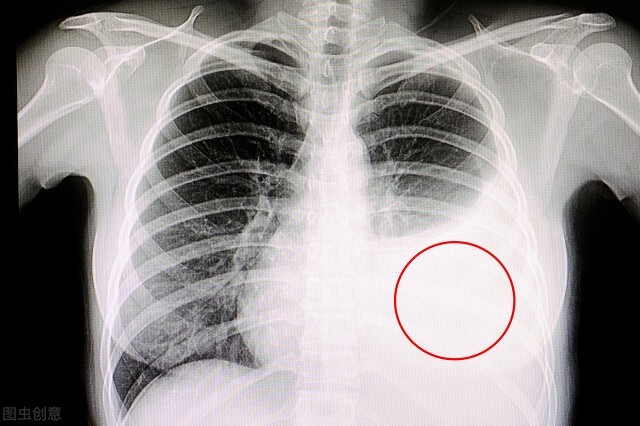

医生紧急地为患者进行床旁胸片检查,竟然发现导致患者呼吸困难的原因竟然是大量的胸腔积液!

大量胸腔积液

由于大学生们对于胸部不适的认识不足,他们认为腹痛和胸部不适根本没有关联,于是在场的同学以及患者本人都没有跟医生提起过胸部不适的问题以及上午剧烈运动的事情。而接诊医生也需要反思的是,既然是急性胰腺炎收治入院,那么常规的胸腹部CT肯定需要检查,如果及时进行了胸部的检查,发现胸腔血管破裂,及时进行治疗,那么悲剧在一定程度上也可以避免。